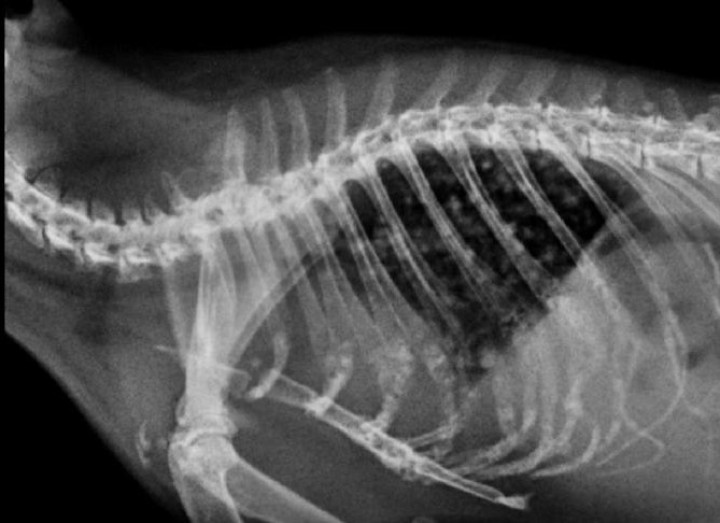

El paciente se recuperó adecuadamente, pero tres meses más tarde acudió a consulta con un cuadro agudo de disnea. En la exploración en consulta del animal se detectó disnea de tipo espiratorio y pérdida de peso (920 g). Se realizaron radiografías que mostraron un patrón nodular pulmonar con punteado difuso de densidad radiopaca, compatible con metástasis (Figs. 11 y 12). Los propietarios decidieron la eutanasia humanitaria del animal y no accedieron a la realización de necropsia.

<p>Radiografía de tórax. Proyección latero-lateral. Se observa un patrón nodular difuso que ocupa todo el campo pulmonar, compatible con metástasis.</p>

Figura 11

Radiografía de tórax. Proyección latero-lateral. Se observa un patrón nodular difuso que ocupa todo el campo pulmonar, compatible con metástasis.

<p>Radiografía de tórax. Proyección ventrodorsal. Se observa un patrón nodular difuso que ocupa todo el campo pulmonar, compatible con metástasis.</p>

Figura 12

Radiografía de tórax. Proyección ventrodorsal. Se observa un patrón nodular difuso que ocupa todo el campo pulmonar, compatible con metástasis.